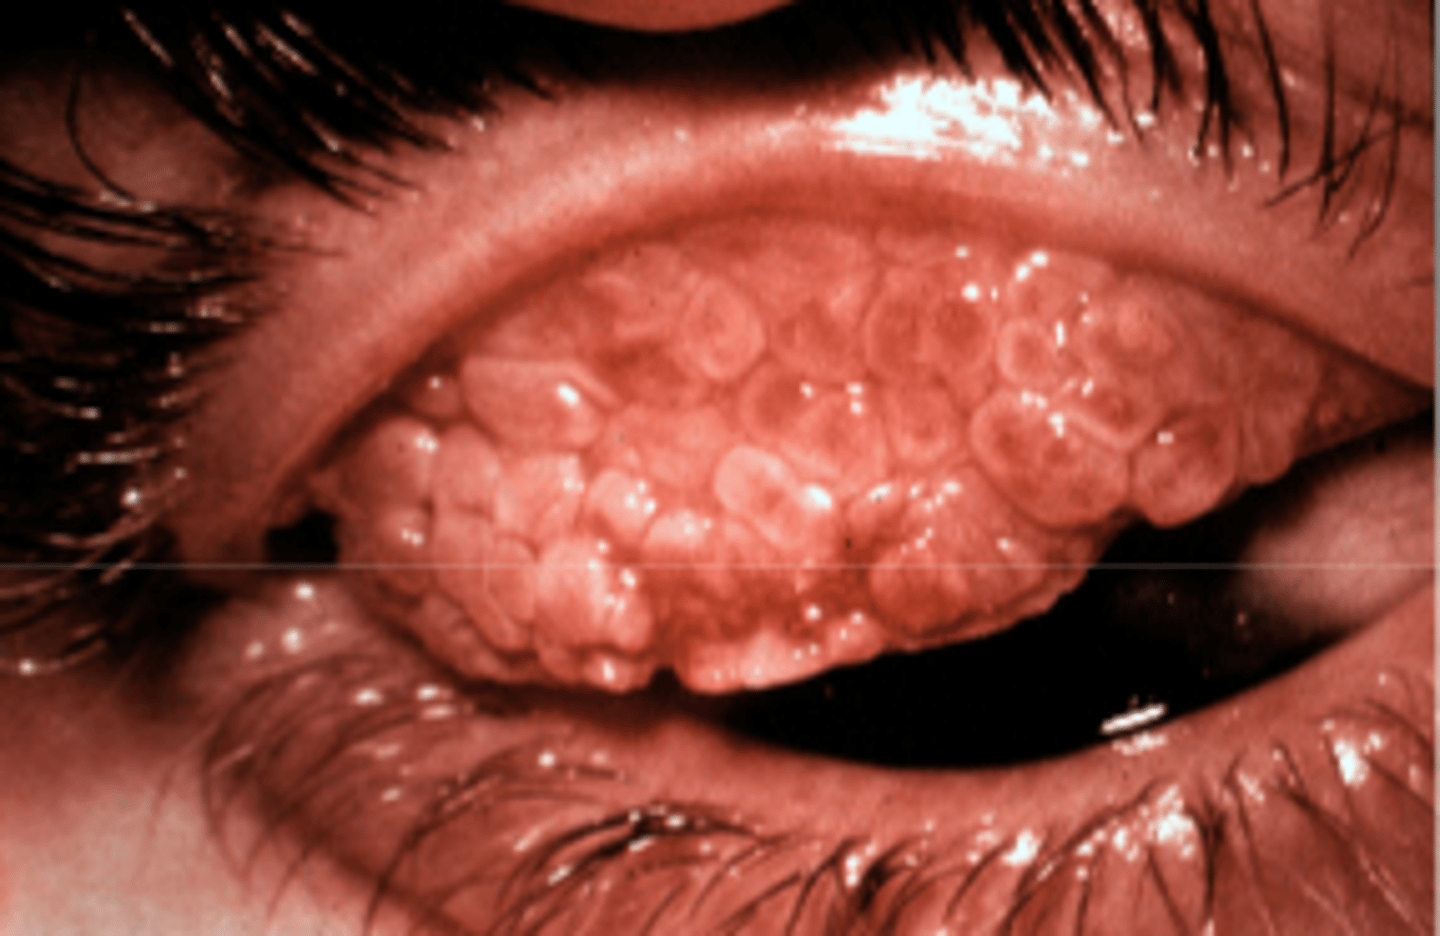

_______ papillae presents with chronic CL over wear, VKC, and AKC

giant